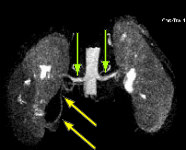

Fig.1 Fig.2 Fig.3

FINDINGS: The ultrasound (not shown) demonstrated dilated collecting system versus extrarenal pelvis on the right. Fig. 1 and Fig. 2 are nephrographic and delayed images through the kidneys. They demonstrate a large dilated right renal pelvis (red arrows) with urine-contrast level and a normal-sized ureter consistent with UPJ obstruction. Fig. 3 is a 3D image from a renal MRA showing an accessory right renal artery (yellow arrows) supplying the right lower pole and impressing upon the right UPJ, explaining the UPJ obstruction. Normal renal arteries are also clearly seen (green arrows)